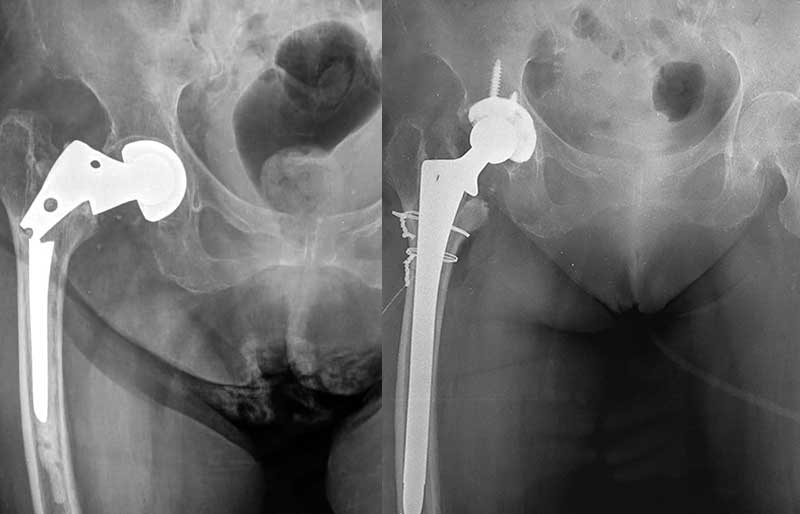

Operasi Penggantian Sendi Panggul

Operasi penggantian sendi panggul adalah suatu operasi untuk mengganti sendi panggul yang rusak dengan sendi buatan yang disebut prosthesis. Penyebab utama kerusakan sendi panggul adalah osteoartritis (baca penjelasan tentang “Osteoartritis”) dan sendi panggul adalah sendi terbanyak kedua setelah lutut yang terserang penyakit ini.

Operasi penggantian sendi panggul merupakan pengobatan terbaik untuk osteoartritis panggul stadium yang berat. Ada empat tujuan operasi ini, yaitu menghilangkan rasa sakit sendi yang telah rusak, memperbaiki lingkup gerak sendi yang sebelumnya kaku dan terbatas, mengembalikan kemampuan penderita melakukan aktivitas harian tanpa rasa sakit, dan meningkatkan kualitas hidup sehingga penderita kerusakan sendi dapat menjalani hidup secara aktif bebas dari nyeri sendi panggul.